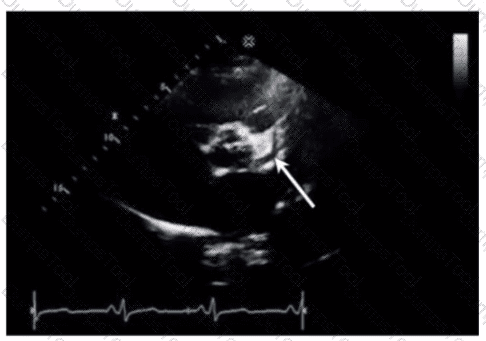

Which step is next in further evaluation of the abnormality shown in this video?